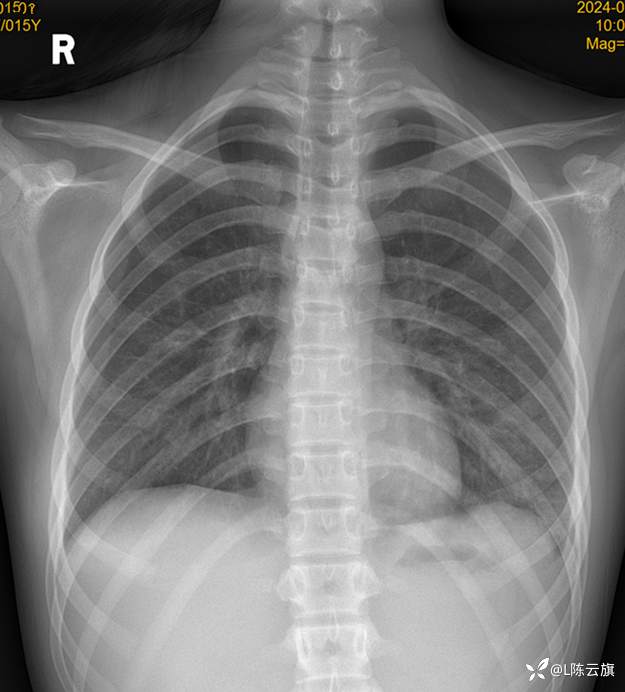

患者女,15岁,精神病住院患者,咳嗽、伴发热两天,余无特殊。